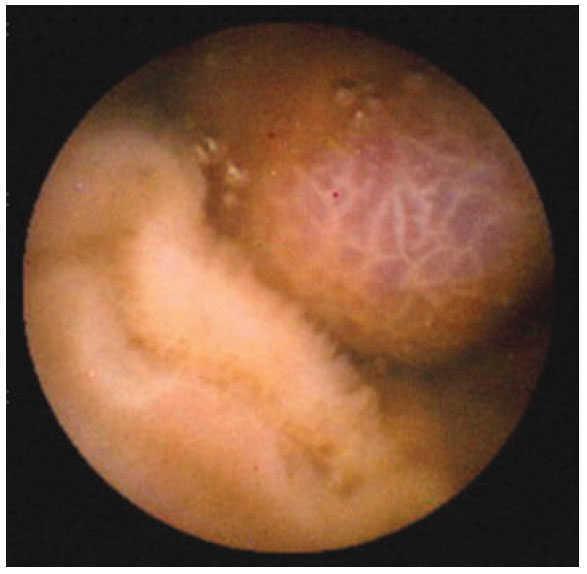

ResultadosEn el periodo comprendido entre enero 2003 a marzo 2008 se realizaron un total de 45 estudios. En 43 pacientes, la cápsula fue deglutida con agua, en dos de ellos tuvo que ser introducida con sobretubo, debido a la incapacidad de los pacientes para deglutirla; procedimientos que se realizaron sin complicaciones y con éxito. El sexo femenino predominó con 27 pacientes (60%) con una mediana de edad de 58.16 años, con intervalo entre los 18 y 84 años. El grupo etáreo más afectado fue el comprendido entre los 71 a 84 años de edad con 14 casos. El motivo de envío más frecuente fue el sangrado gastrointestinal de origen oscuro, con 32 casos (71.11%). Los siguientes fueron diarrea crónica con cinco casos (11.11%), dolor abdominal tres casos (6.67%) y melena tres casos (6.67%). Los hallazgos reportados incluyeron: Sin causa 18 casos (40%), erosiones en 10 casos, algunas de ellas relacionadas con AINE (22.20%) (figura 2). Alteraciones vasculares en ocho casos (17.76%), pólipos en seis casos (13.32%), gastropatía nodular con dos casos (4.44%), tumoraciones en dos casos (4.44%) (figuras 3 y 4), y con un caso (2.22%) cada una de las siguientes patologías: pseudopoliposis antral, diverticulosis y sangrado activo en el Treitz de causa no determinable. En general, el procedimiento fue bien tolerado. No se presentaron complicaciones durante ni posterior al procedimiento. No se reporta en ningún caso la retención de la cápsula en el tubo digestivo. Mención aparte, aunque no fue motivo del presente estudio, será importante contar con el número de pacientes que fueron sometidos a estudios complementarios (serologías, enteroscopias, laparotomías, etc.), ya que con ello se podrán tener más argumentos para definir el lugar que actualmente ocupa la videocápsula en nuestro país y tal vez con más investigación de este tipo, poder sugerir un algoritmo de estudio para pacientes con hemorragia de origen oscuro.

Figura 3. Pólipo adenomatoso de yeyuno.